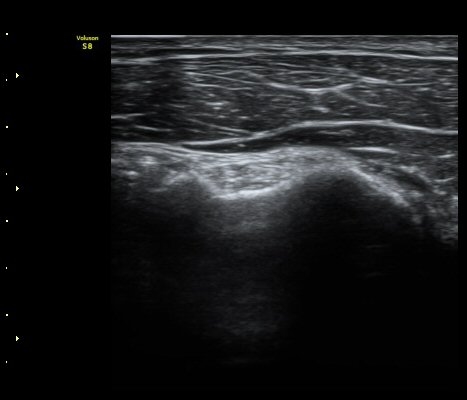

¿À±¸µ¹±â Á¾´Ü¸é°Ë»ç½Ã ¿À±¸ µ¹±â ³»Ãø, ¿À±¸µ¹±â ¾Æ·¡¿¡ ¼ö¾×Àú·ù°¡ °üÂûµÈ´Ù(±×¸² 5, 6).